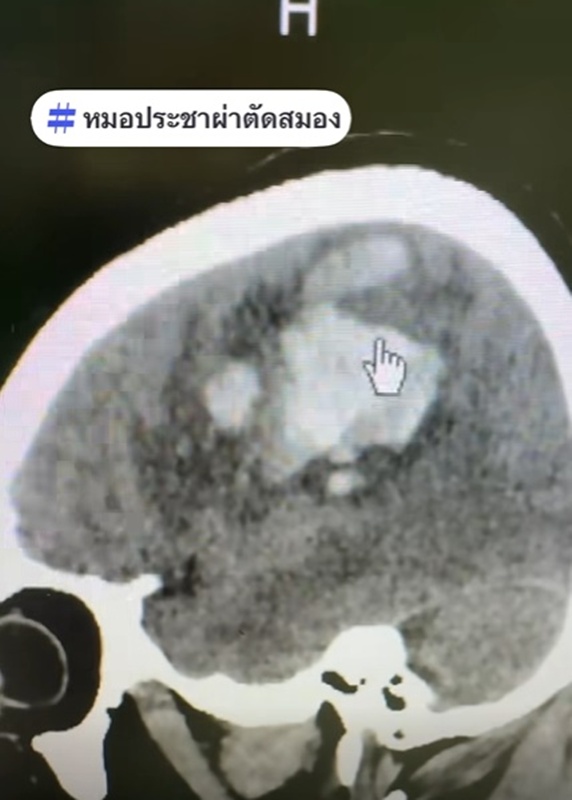

วันที่ 9 มกราคม 2569 หมอประชาผ่าตัดสมอง เล่าเคส ผู้ป่วยชายวัย 59 ปี ตื่นเช้ามายกแขน-ขาซีกซ้ายไม่ได้ พอสแกนสมองพบจุดขาว ๆ ก้อนใหญ่ นั่นคือ เลือดที่ออกในสมอง จึงรีบผ่าตัดเป็นการด่วน ซึ่งผลการผ่าตัดสำเร็จไปได้ด้วยดี

สำหรับสาเหตุที่ทำให้เส้นเลือดในสมองแตกกรณีนี้คือ ความดันโลหิตสูงและนอนกรน รวมถึงอากาศหนาวจะทำให้คุมความดันโลหิตยากขึ้น เส้นเลือดในสมองจะชอบแตกตอนเช้าตรู่หน้าหนาว หลอดเลือดจะหดตัวจากอากาศที่หนาวเย็น ยิ่งเคสนี้มีนอนกรนและหยุดหายใจตอนหลับ ยิ่งทำให้ความดันโลหิตสูง